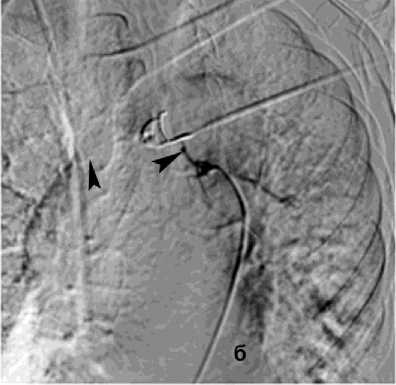

Рисунок 6. Ангиограмма БА у пациента с опухолью заднего средостения и прорастанием лёгкого, ЛК2Б: а – извитость и усиление лёгочного рисунка; б – состояние после эмболизации – окклюзия БА

Figure 6. Angiogram of the BA in a patient with posterior mediastinal tumor and lung invasion, PH grade 2B: a – tortuosity and increased pulmonary vascularity; б – status post embolization – occlusion of the BA

Первым этапом в процессе диагностики бронхоскопии через фибробронхоскоп выполняли промывание трахеи холодным физиологическим раствором, инъекции адреналина (рис. 5). При наличии и доступности определённого источника кровотечения использована электрокоагуляция с ис- сечением опухоли бронха 4 (2,7%), бужирование и стентирование бронха 11 (7,3%). При интенсивном кровотечении в 13 (8,7%) случаях выполняли брон-хоблокацию. Удаление блокатора осуществляли на 5–8 сутки. В одном случае бронхоблокация сочеталась со стентированием аорты. Проведённый анализ ангиограмм позволил выявить косвенные признаки ЛК. В большинстве случаев наблюдалось усиление кровоснабжения зоны поражения независимо от выявленной патологии (рис. 6, а). Локализация сосудистых изменений соответствовала данным, полученным при таких диагностических методах как ФБС и КТ. Эти ангиографические признаки не имеют прямого отношения к ЛК, но достаточно полно характеризуют его причину в силу специфичности семиотики различных лёгочных заболеваний. Прямые признаки экстравазации мы наблюдали в одном случае при наличии аортобронхиального свища (рис. 9, а).

Эмболизация бронхиальных артерий (ЭБА) является радикальным методом лечения ЛК из системы бронхиальных артерий и выполнена в 134 (89,9%) cлучаях. ЭБА часто считается первой линией лечения при массивном ЛК. Эмболизация правой бронхиальной артерии проведена в 68 (45,1%) случаях, левой – в 32 (21,1%), обеих бронхиальных артерий - в 34 (22%) случаях (рис. 6).